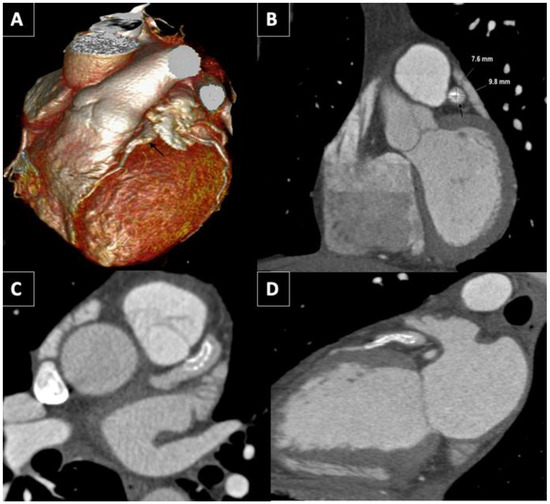

The patient underwent an emergent coronary angiography due to this anterior ST-segment-elevation myocardial infarction. The coronary angiography revealed CAA, extending from the left main stem to the proximal segment of the anterior descendent artery (LAD) and a thrombotic occlusion (TIMI 1 flow) of its distal segment (Figure 1A/Video S1). Two guidewires were crossed to the distal segment of the LAD and the first diagonal. After percutaneous thrombus aspiration, the flow of the LAD was not restored. A perfusion of a glycoprotein IIb/IIIa inhibitor class (eptifibatide) was initiated during the procedure. A microcatheter was then crossed to the distal segment of the LAD and contrast was infused from the microcatheter and support catheter simultaneously in order to check the distal vessel’s diameter and to confirm the extension of the occlusion (Figure 1B/Video S1). Then, a 2.75 × 28 mm drug-eluted stent was implanted covering the occlusion, with its size adjusted to the distal segment of the aneurysm (Figure 1C).

An intravascular ultrasound (IVUS) was performed thereafter, showing the stent “floating” in the aneurysm covered by thrombus (Figure 1E–H). A post-dilatation with a 3 non-compliant balloon in the distal segment of the stent improved the distal stent apposition and a post-dilatation with a 5 mm non-compliant balloon in the proximal segment resulted in a “funnel”-like shape (Figure 1D/Video S2). The LAD regained normal coronary flow (TIMI III).

Figure 1. (A) CY showing a CAA with a maximum diameter of 8.49 mm (white double arrow). (B) CY displaying simultaneous contrast infusion from the microcatheter and support catheter. (C) CY showing aneurysm after stent implantation. (D) CY displaying the “funnel” shape of the distal segment of the aneurysm after the post-dilatation. (EH) Coronary IVUS showing the stent apposition along the CAA in the ADA showing the stent “floating” in the aneurysm surrounded by thrombus. RAO: Right anterior oblique. LAO: Left anterior oblique.